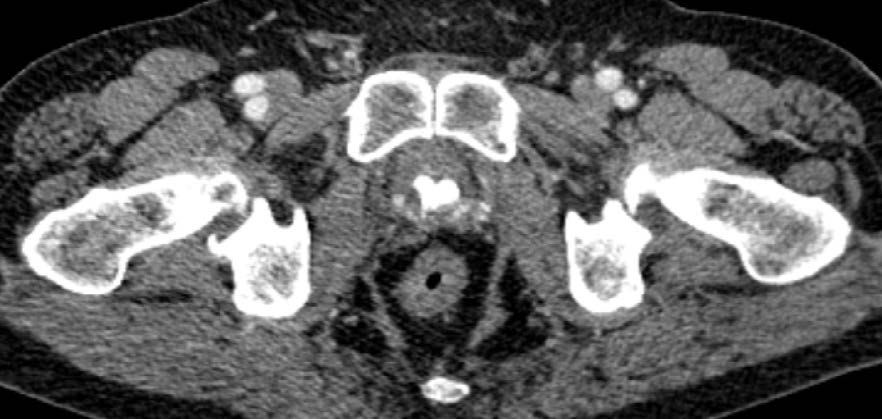

The third patient underwent endovideosurgical RPE with preservation of both NVBs also using Hem-o-Lok clips. The postoperative period was uneventful; the patient holds urine from the first day of catheter removal. There was a gradual deterioration of urination, thinning of the urine stream and occasional impurity of blood in the urine after 4 years and 2 months after surgery. The patient was taking alpha-adrenoblockers and phytopreparations with no significant positive effect. During examination, CT scan of the pelvis revealed an irregularly shaped bladder concrement fixed to its posterior wall with the dimensions of 3×4 cm (Fig. 4). The patient underwent urethrocystoscopy with laser cystolithotripsy. Six Hem-o-Lok clips were detected after stone fragmentation, immersed in the thickness of the posterior wall of the urinary bladder cervix at different depths (Fig. 5). There was performed photovaporization of scar tissues around the clips with their subsequent removal with forceps. The postoperative period proceeded without complications, the urethral catheter was removed on the fourth day. The complaints of dysuria and hematuria are resolved; the patient holds urine completely.

Fig. 4. CT scan of a concrement bladder